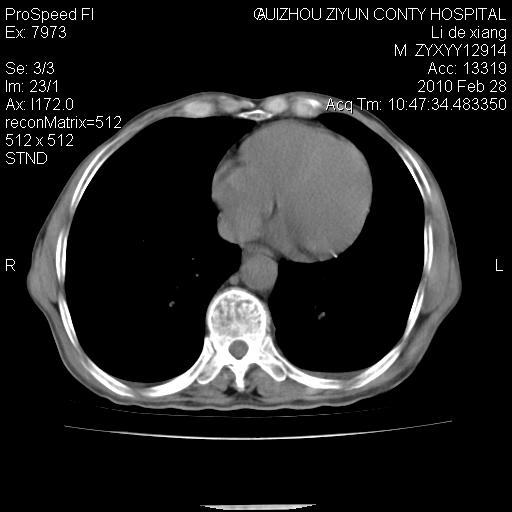

标题: CT24776:男 71Y 咳嗽咳痰胸痛两月,伴声音嘶哑。 [打印本页]

标题: CT24776:男 71Y 咳嗽咳痰胸痛两月,伴声音嘶哑。

左侧中央型肺癌伴左肺上叶阻塞性肺炎及节段性不张可能性大,建议纤支镜检查!

左侧中央型肺癌伴左肺上叶阻塞性肺炎及节段性不张可能性大,建议纤支镜检查!纵隔淋巴结转移.

左侧中央型肺癌伴左肺上叶阻塞性肺炎及纵隔淋巴结转移。

左肺门部肿块,伴左上肺斑块影,周边模糊,支持左肺中央型肺癌伴节段性不张及阻塞性肺炎,结合支气管镜检查。

患者有声音嘶哑,若时间长了,没改变,喉镜检查无异常,可考虑左侧喉返神经受累,因为:左侧喉返神经绕主动脉弓或肺动脉韧带的主动脉端,沿气管与食管之间的沟上行至颈部.

支持肺癌.

左上叶支气管狭窄,阻塞性病变,肺门肿块,纵隔及肺门淋巴结增大,中央性肺癌

左肺中央型肺癌并阻塞性改变、纵膈 淋巴结转移

左侧中央型肺癌伴左肺上叶阻塞性肺炎及纵隔淋巴结转移

支持 左肺中央型肺癌伴左肺上叶阻塞性肺炎,纵隔淋巴结转移。